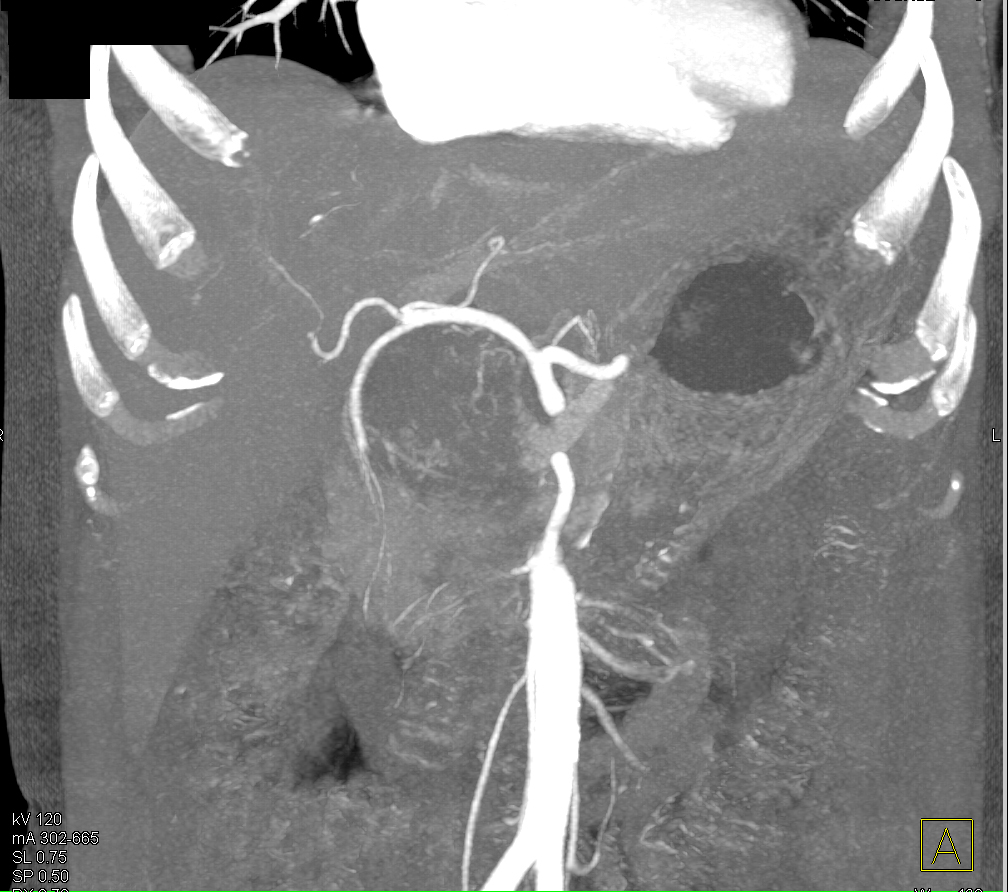

8) In this 50ish year old with chest pain the best dx is?

coronary artery plaque

aberrant origin of the RCA

aneurysm of the LAD

pulmonary embolism